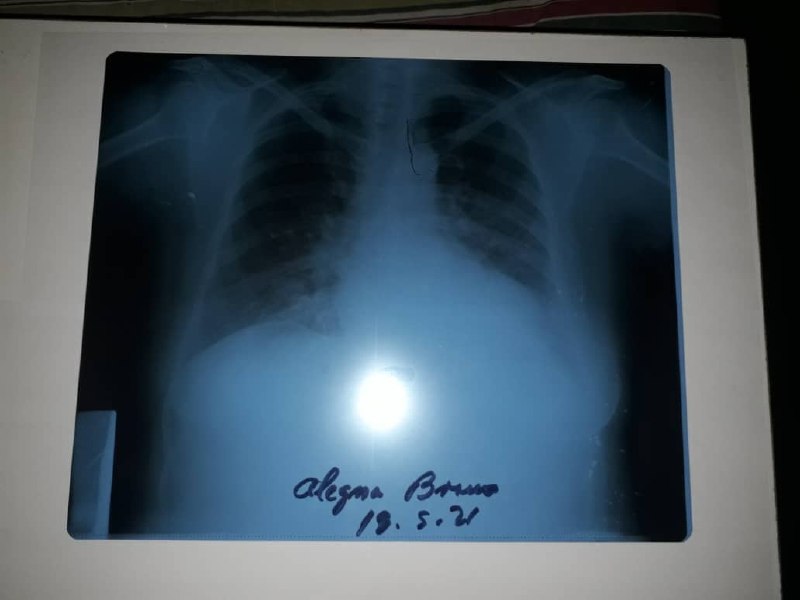

This is a plaque of her lungs

This lady you can see in the photo is called Alegna Bravo. She is 59 years old. She lives here in Maracaibo, Venezuela. She is a coronavirus patient, and a victim of atrocious pneumonia that kept her hospitalized recently. She is one of my dear aunts, wife of one of my late grandfather's brothers. She is a very responsible person and a great housewife, a widowed woman who also saw her husband die at an early age.

My Aunt Alegna has been suffering from severe symptoms of coronavirus, and she has had to need oxygen, as well as a lot of medication and special treatments. She is a fighting mother who deserves to keep fighting and living so that she can accompany the only child she has left in the country.